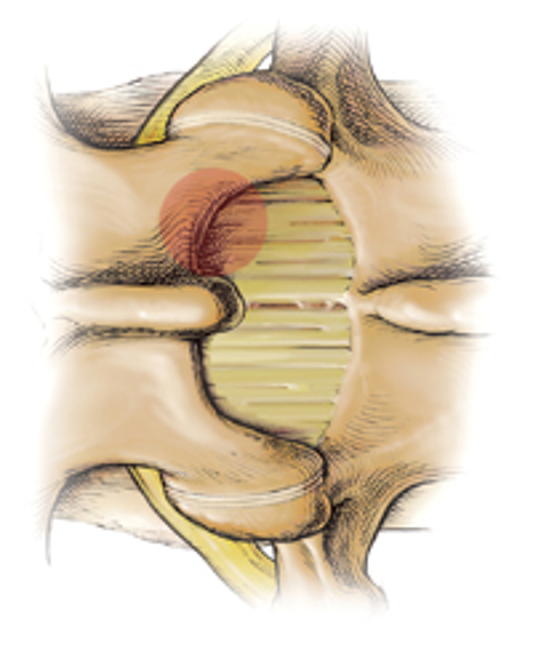

后路椎间盘镜下髓核摘除术

技术特点采用微创技术,皮肤创口仅1.5cm左右,不剥离椎旁肌,保留棘上、棘间韧带和大部分上、下关节突以及未破损的纤维环和后纵韧带,尽可能保持脊柱的稳定性。去除了突出的髓核组织、肥厚的黄韧带及增生内聚的关节突等神经致压因素,从而使患者获得根治的疗效。

技术要点

定位

定位是MED手术成败的关键。

横断面上,距棘突中点0.5~1cm,矢状面上取椎间盘中位线的延长线与腰部皮肤的交点。

定位针朝向上位椎板插入,上下滑动针尖,使针尖位于上位椎板下缘的骨质上。

手术通道安装

将定位针置于上位椎板下缘骨质上,防止插入肌肉扩张管时将导针推入椎管内。

用扩张管来回刮擦椎板及黄韧带外软组织,直到出现骨擦感。这样可以减少通道内软组织。

通道管的方向:矢状面与椎间隙平行,横断面大致与棘突平行、与椎板垂直。

进入椎管方法

椎板间隙入路:1、椎板下方入路;2、椎板下缘关节突内侧入路

椎板骨性入路

侧方入路

黄韧带在椎板下缘处最薄弱,而椎管内以神经根外上方(肩部)最安全,因此最常选用椎板下缘关节突内侧入路。